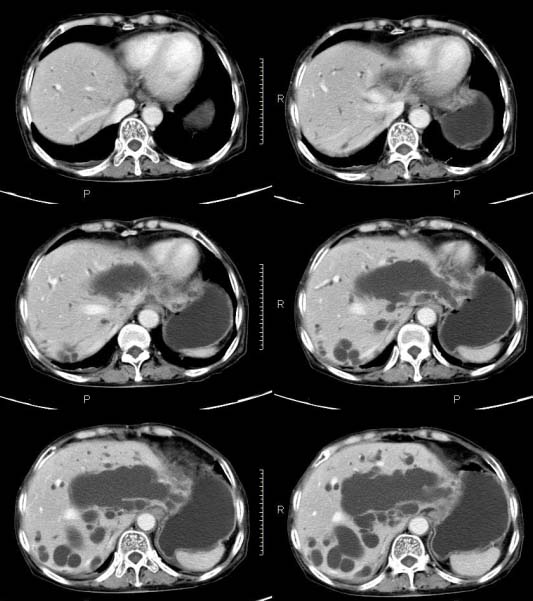

女,71岁,腹痛、腹胀、黄疸20余天,b超示肝内外胆管高度扩张内伴絮状物质(未提示梗阻部位或结石影),经抗炎解痉治疗后,肝功能有所好转,但胆道梗阻状态并未减轻。患者曾于1970年代做过胆囊切除术,1997年因胰腺炎而手术;且患者有糖尿病10余年。ct图片传了静脉期,未传动脉期了,最后一序列为3.2mm薄扫,请各位同仁仔细看看,确定一下胆管梗阻的部位,是炎性梗阻还是肿瘤性梗阻,是否与胰腺炎有关系,扩张胆总管中段前缘是否是胰管。请高手们最好用图示来指出梗阻部位。

扩张的胆管直达胰头,但胰头增大又不明显,且无异常密度影。考虑壶腹部占位。

请大家看看扩张的胆总管内见一弧线形间隔,怎样解释?

肝内外胆管显著扩张,考虑先天性胆管囊肿(ⅳ型)。

肝内胆管远侧、近侧不比例扩张,以近侧为明显。胆总管扩张。考虑先天性胆管囊肿(ⅳ型)。